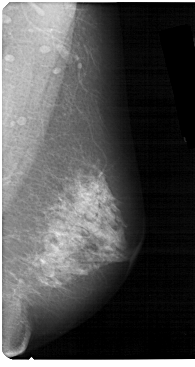

ics_version 1.0 filename A-1317-1 DATE_OF_STUDY 9 3 1992 PATIENT_AGE 68 FILM FILM_TYPE REGULAR DENSITY 4 DATE_DIGITIZED 28 7 1998 DIGITIZER HOWTEK 43.5 SEQUENCE LEFT_CC LINES 5146 PIXELS_PER_LINE 2236 BITS_PER_PIXEL 12 RESOLUTION 43.5 OVERLAY LEFT_MLO LINES 5491 PIXELS_PER_LINE 2611 BITS_PER_PIXEL 12 RESOLUTION 43.5 OVERLAY RIGHT_CC LINES 5281 PIXELS_PER_LINE 2341 BITS_PER_PIXEL 12 RESOLUTION 43.5 NON_OVERLAY RIGHT_MLO LINES 5491 PIXELS_PER_LINE 2911 BITS_PER_PIXEL 12 RESOLUTION 43.5 NON_OVERLAY |